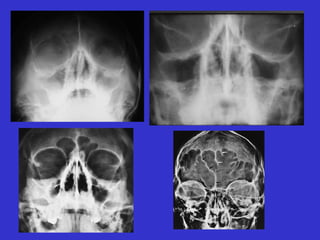

Este documento describe las diferentes proyecciones radiográficas utilizadas para examinar los senos paranasales, incluyendo las proyecciones básicas de Caldwell, Waters lateral y las proyecciones especiales como Hirtz y Waters mentonasal. También describe las diferentes estructuras anatómicas que componen el complejo ostiomeatal anterior y posterior de los senos paranasales.